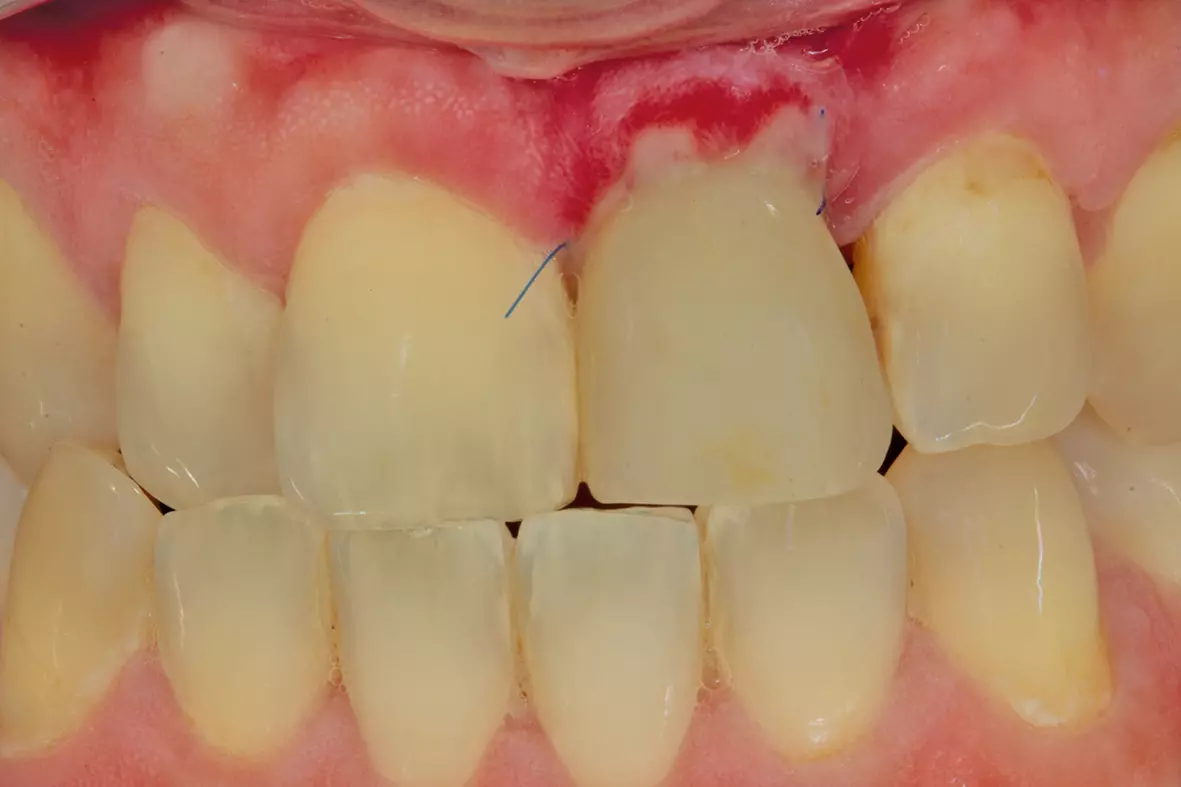

Nach drei Monaten folgte die Freilegung (Abb. 17). In der Operation erfolgte zunächst unter dem Mikroskop wieder die krestale Schnittführung an derselben Stelle wie bei der Implantation unter Erhalt eines einige Millimeter breiten Streifens befestigter Mukosa. Dann wurde der Lappen mit einem Papillenraspatorium zuerst etwas angehoben und dann scharf epiperiostal weiterpräpariert. Die Verschlussschraube wurde aus dem Implantat entfernt und die provisorische Krone eingegliedert. Der interdentale Wundverschluss erfolgte mit Prolene 6.0 (Ethicon, Johnson & Johnson Medical) in Form von vertikalen Matratzennähten (Abb. 18).